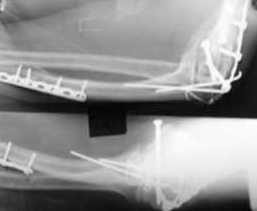

Уважаемые коллеги! Нужен Ваш совет, Подскажите пожалуйста, как можно в дальнейшем этому больному помочь. В марте первая операция, пришлось оперировать на 16 сутки в виду инфицированных садин и анемии. Заживление первичным натяжением,раняя разработка после операции, а через 2 нед болевой синдром,и постепенно движения в локтевом суставе ограничились до полного анкилоза. Повторно через 4 месяца вторая операция" артролиз,удаление оссификатов, удаление фиксаторов, реостеосинтез этой же реконструкционной пластиной и винтом" интраоперационно после удаления оссификатов и фиксаторов обнаружил, что перелом не сросшиеся, поэтому пришлось синтезировать заново. Зажило рана первично, объем движений в локтевом суставе сгибание 70, разгибание160, ротационные движения востановились полностью,вроде бы успокоились. Опять постепенно в течении 8 нед после повторной операции постепенно движения ограничились до 80 - 110, на снимке оссификат. Снимки во вложении, буду рад Вашим советам. Спасибо!С уважением Шухрат.